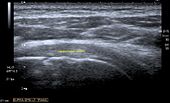

Longitudinal ultra sonography of the supraspinatus tendon

Ultrasound

There are several advantages of ultrasound. It is relatively cheap, does not emit any radiation, is accessible, is capable of visualizing tissue function in real time, and allows the performance of provocative maneuvers in order to replicate the patient’s pain.[25] Those benefits have helped ultrasound become a common initial choice for assessing tendons and soft tissues. Limitations include, for example, the high degree of operator dependence and the inability to define pathologies in bones. One also has to have an extensive anatomical knowledge of the examined region and keep an open mind to normal variations and artifacts created during the scan.[26]

After the introduction of high-frequency transducers in the mid-1980s, ultrasound has become a conventional tool for taking accurate and precise images of the shoulder to support diagnosis.[28][29][30][31][32]

Adequate for the examination are high-resolution, high-frequency transducers with a transmission frequency of 5, 7.5, and 10 MHz. To improve the focus on structures close to the skin an additional "water start-up length" is advisable. During the examination the patient is asked to be seated, the affected arm is then adducted and the elbow is bent to 90 degrees. Slow and cautious passive lateral and/or medial rotations have the effect of being able to visualize different sections of the shoulder. In order to also demonstrate those parts which are hidden under the acromion in the neutral position, a maximum medial rotation with hyperextension behind the back is required.[33]

To avoid the different tendon echogenicities caused by different instrument settings, Middleton compared the tendon’s echogenicity with that of the deltoid muscle, which is still lege artis.[34][35]

Usually the echogenicity compared to the deltoid muscle is homogeneous intensified without dorsal echo extinction. Variability with reduced or intensified[36] echo has also been found in healthy tendons. Bilateral comparison is very helpful when distinguishing and setting boundaries between physiological variants and a possible pathological finding. Degenerative changes at the rotator cuff often are found on both sides of the body.[37] Consequently, unilateral differences rather point to a pathological source and bilateral changes rather to a physiological variation.[35]

In addition, a dynamic examination can help to differentiate between an ultrasound artifact and a real pathology.[38]

To accurately evaluate the echogenicity of an ultrasound, one has to take into account the physical laws of reflection, absorption and dispersion. It is at all times important to acknowledge that the structures in the joint of the shoulder are not aligned in the transversal, coronal or sagittal plane, and that therefore during imaging of the shoulder the transducer head has to be held perpendicularly or parallel to the structures of interest. Otherwise the appearing echogenicity may not be evaluated.[39]